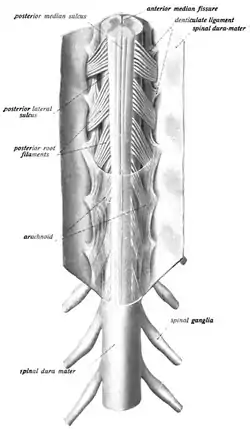

The spinal cord with spinal nerves. | |